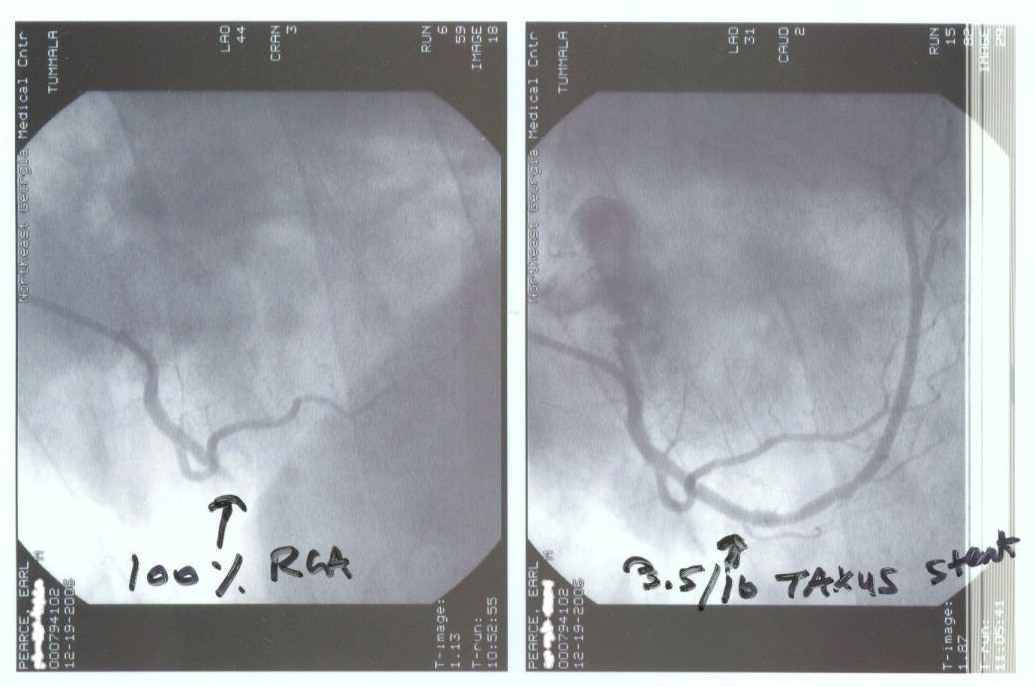

Heart attack and taxus stent 12/19/2006. Before and after photos: “God protects the ignorant sometimes” I must have a purpose....:)

Heart_20061219a